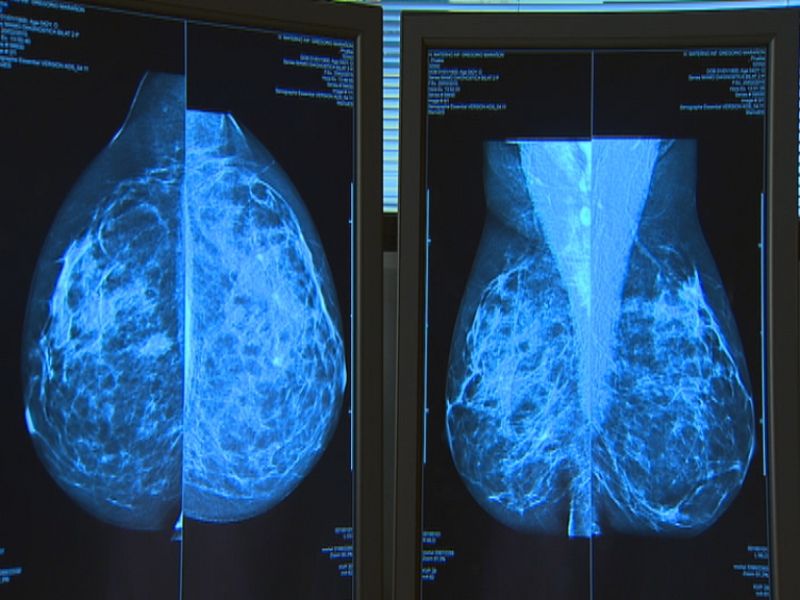

La polémica por los retrasos en el diagnóstico del cáncer de mama sacude Andalucía. La Asociación de Mujeres con Cáncer de Mama (AMAMA) denuncia que al menos 50 pacientes sevillanas han acudido a ellas denunciando un diagnóstico tardío y ha exigido a la Consejería de Salud que revise todas las mamografías hechas en los últimos cinco años. Ante esta situación, la Junta ha pedido disculpas y ha prometido que las afectadas podrán acceder a un "circuito preferente".

Hernández ha recordado que este cribado invita cada año a medio millón de mujeres y que, de enero a agosto, se han diagnosticado 1.800 cánceres de mama que, de otra forma, no se habrían detectado. "Desde el minuto uno estamos revisando el circuito para aquellas mujeres que en la mamografía pueden tener algunas lesiones con imágenes dudosas", ha asegurado la consejera, quien ha añadido que cuando existen lesiones "con claros signos de malignidad" sí se envía una comunicación por teléfono a las afectadas.